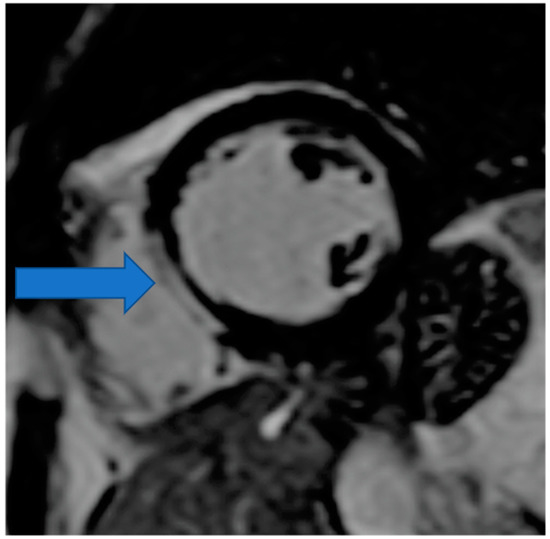

4.5. Myocardial Edema-Fibrosis Assessment